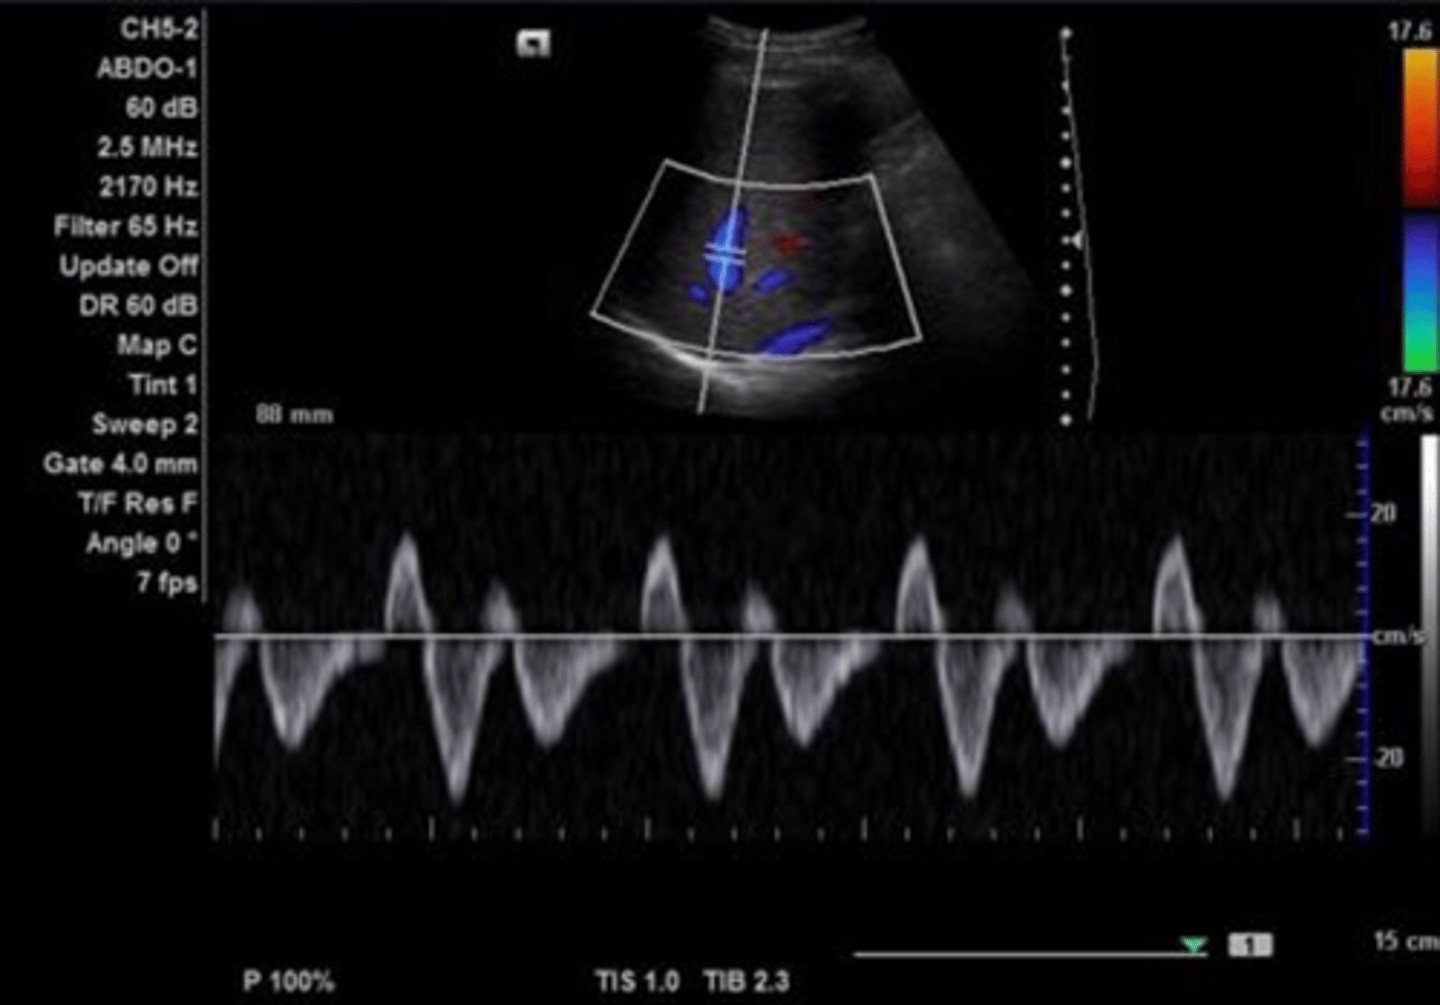

Hepatic Vein Doppler Waveform

Triphasic

Antegrade & retrograde flow - cardiac pressure changes

Hepatic Vein Doppler

S wave: ventricular systole

D wave: atrial filling

A wave: atrial contraction

Inspiration depresses systolic wave

Exhalation augments systolic wave

Valsalva diminishes pulsatility